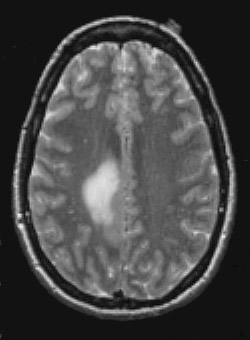

This T2 weighted magnetic resonance imaging (MRI) scan in transverse view demonstrates an infiltrative mass involving the posteromedial right frontal lobe and parietal lobe, consistent with a glioma.